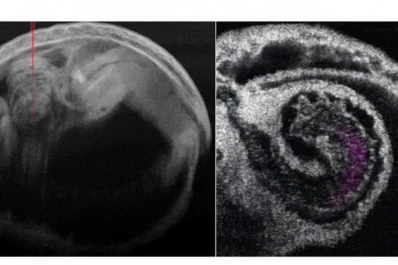

Nuevo método: ahora se puede estudiar el corazón en 4D

El estudio se ha hecho en ratones por ahora y para analizar corazones en estado embrionario.